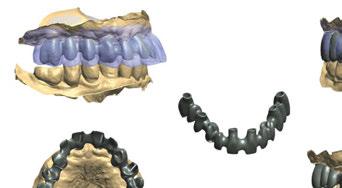

Hoy en día, debido a las altas demandas estéticas de muchos pacientes, la Implantología ha ido evolucionando, sobre todo respecto a protocolos de tratamiento, para poder realizar tratamientos predecibles y exitosos a nivel estético, biológico y funcional. Actualmente disponemos de herramientas digitales (escáneres, CBCT, software de planificación, impresoras 3D, etc.), que nos permiten optimizar tanto la fase previa de estudio y planificación como la fase quirúrgica y protésica posterior. Estas herramientas toman un papel importante en los casos de Implantología inmediata y provisionalización inmediata, pudiendo preparar previamente a la cirugía, guías quirúrgicas y provisionales de carga inmediata (1).

Cuando debemos de afrontar un caso de Implantología múltiple y provisionalización inmediata, todos estos factores cobran aún más importancia (7-9). Como explicaremos a continuación en el caso clínico, para lograr un resultado óptimo, deberemos iniciar nuestro tratamiento a partir de encerados digitales, que nos permitan simular la rehabilitación definitiva (10). A partir de aquí podremos planificar la posición tridimensional correcta de nuestros implantes protéticamente guiados, ayudándonos de guías quirúrgicas, tanto en las regeneraciones óseas previas como en la cirugía implantológica.

-Escáner intraoral mediante iTero Element™2 con el fin de obtener modelos digitales (archivos STL) (Figura 3).

-Protocolo de planificación digital del caso mediante RealGUIDE® (STL+DICOM) (Figura 4) (Cuadro 1).

A continuación, para la planificación de los implantes dentales y el diseño de la férula de cirugía guiada se usó la plataforma digital RealGUIDE®. Para ello se realizó el matching, por un lado, del archivo STL del encerado digital; y, por otro, del archivo 3D. De esta manera, se pudo analizar el tejido óseo residual apical a cada diente y la posición de la raíz respecto a las corticales vestibular y palatina. También se estudió la relación de los contornos óseos con los tejidos blandos y con la posición final de los márgenes cervicales de la restauración protésica, pudiendo así planificar la posición 3D correcta de los implantes. En esta primera fase se diseñó una férula quirúrgica para la elevación de seno bilateral a partir del software RealGUIDE™, que nos sirvió de guía para el diseño de las ventanas de acceso. Esta férula se imprimió con la impresora 3D Formlabs® (Figura 7)

A los 6 meses de cicatrización, se realizó un nuevo CBCT, obteniendo un nuevo archivo DICOM que alineamos con el STL del encerado. De esta manera, se planificó la posición de los implantes a 4 mm del margen de la restauración final y se diseñó y confeccionó la férula de cirugía guiada dentosoportada en 12-13 y 22-23, la cual imprimimos con la impresora 3D Formlabs®. El provisional

de carga inmediata lo diseñamos con el programa de diseño 3D Exocad® a partir del encerado y se imprimió también en clínica con la misma impresora 3D (Figuras 14-16).